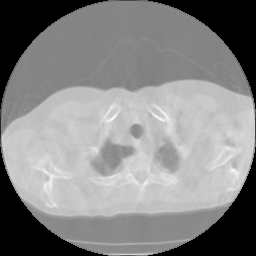

Limited angle CT reconstruction is a very challenging ill-posed issue and of great interest in several clinical applications, such as digital breast tomosynthesis [1], dental tomography [2], short exposure time [3], etc. In a limited-angle CT scan, the projection data can be obtained in less than 180superscript180180^{\circ} angular range, and the data insufficiency degrades reconstruction quality with streaking artifacts(fig 1 (a)(b)).

Figure 1: Qualitative illustration of the task: (a) given a limited-angle sinogram; (b) automatic inpainting result using our sinogram inpainting network (SIN); (c) ground truth sinogram; (d) reconstruction result of state-of-art iterative SART method with TV normalization; (e) our method output; (f) ground truth image